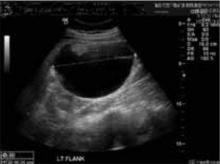

FIGURE 1 Imaging at 9 weeks of gestation

Teratoma or solid component of the collision tumor.At 7 weeks’ gestation, I performed her first pelvic exam, during which I palpated a mass in the left adnexa. The patient was asymptomatic. US imaging revealed a complex cystic mass measuring 4.7 × 4.4 × 3.7 cm on the left ovary and a viable 9-week gestation in the uterus (FIGURE 1). A repeat US at 18 weeks revealed that the mass had increased in size to 7.5 × 6.9 × 3.7 cm (FIGURE 2). The patient (and her mother) refused resection, so a follow-up scan was scheduled. The patient remained asymptomatic.